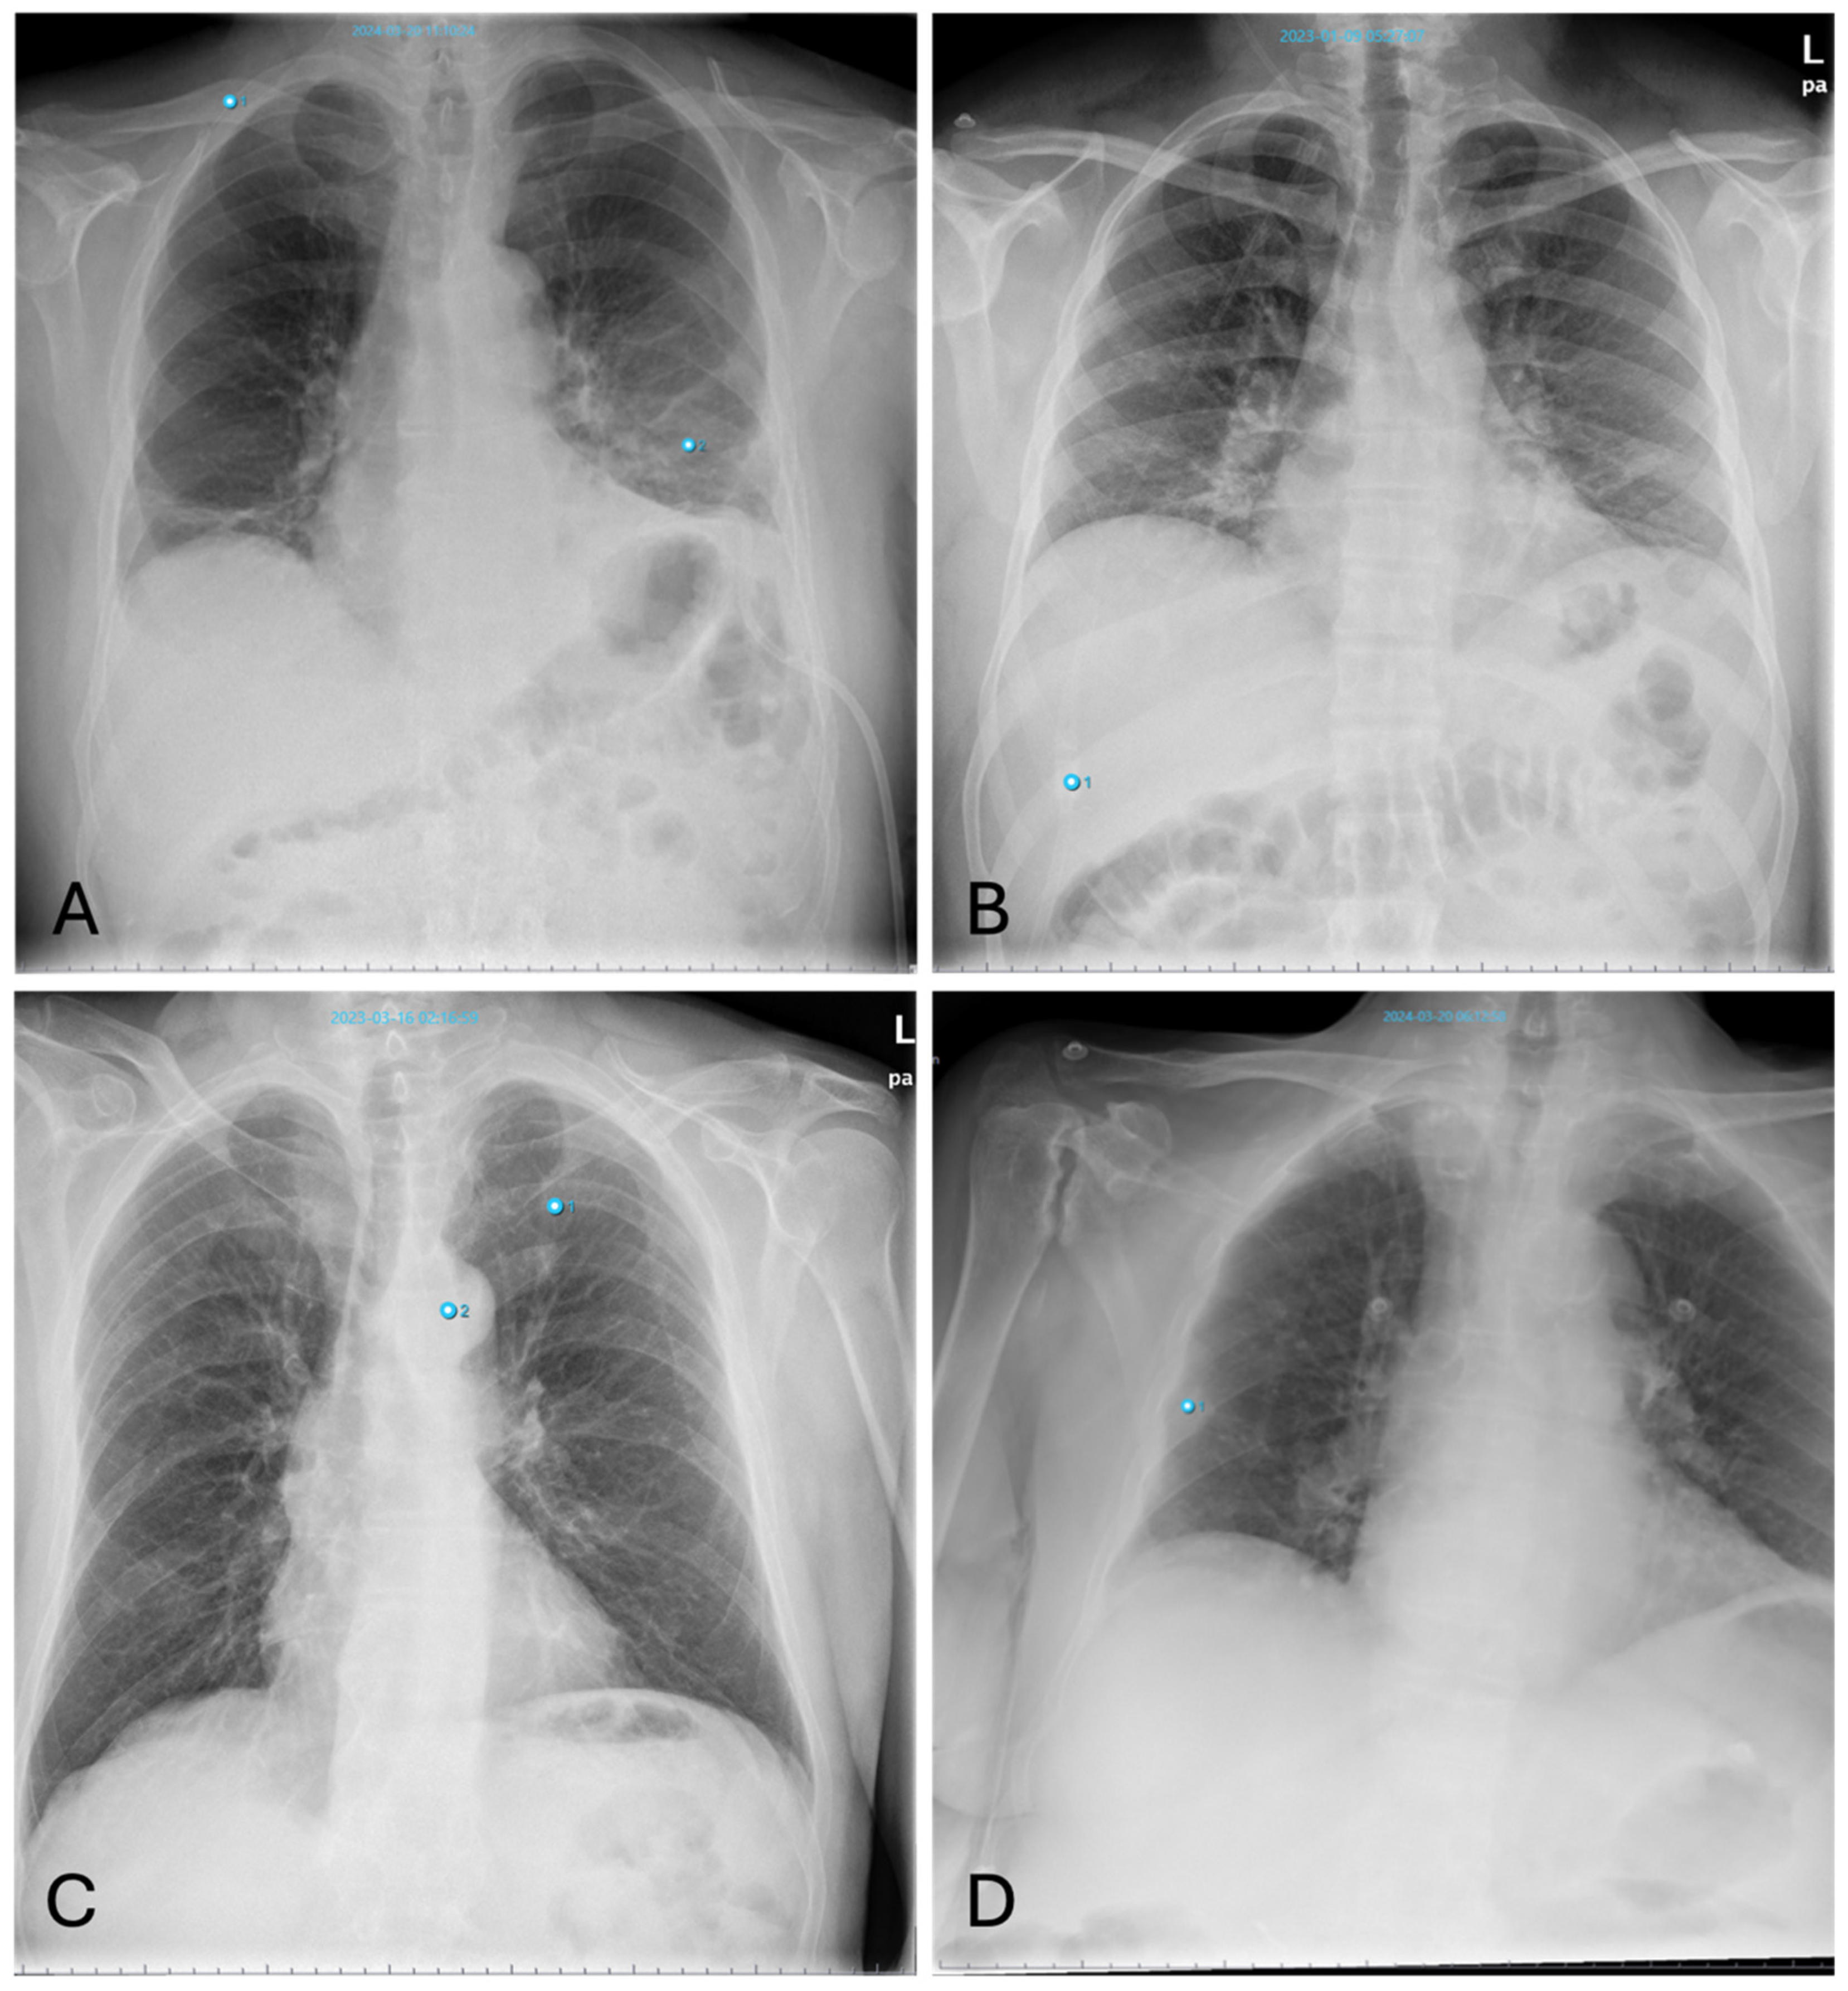

3.4.2. Pneumonia

False-positive AI findings occur in younger patients with dense breast tissue, as well as with increased vascular markings indicative of congestion (Figure 6A). The AI also frequently interprets poorly defined lung masses as pneumonic infiltrates.

False-negative results for pneumonia often occur in cases of early pneumonic infiltration or when the infiltrates are located retrocardially. Similarly, pneumonia near the hilum is frequently undetected by the software (Figure 6B).

Figure 6. Inconsistencies of pneumonia diagnoses: (A)—false-positive AI interpretation of dense breast parenchyma as pneumonia in a young woman (Note: other finding incorrectly labelling “aortic abnormality”); (B)—false-negative interpretation of pneumonia. X-ray shows pneumonic congestion in the right lower lobe not detected by AI (Note: other findings incorrectly labelling “aortic abnormality” and “pneumonia”).